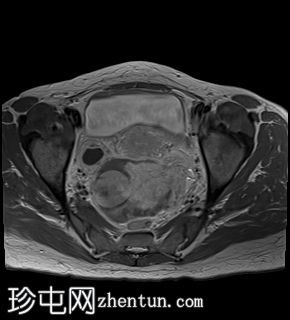

冠状位

T2加权像

2.jpg

左侧卵巢增大、水肿,位置异常,卵泡呈周边排列

左侧卵巢血管扭转,呈漩涡征

上述左侧卵巢增大、水肿、位置异常、卵泡呈周边排列、实质出血的特征提示卵巢扭转伴出血。梗死。